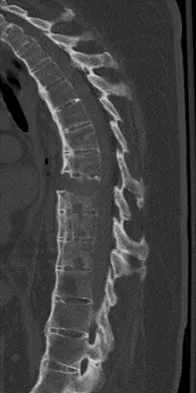

A 44-year-old woman has had lower extremity dysesthesias, urinary incontinence, and has been unable to walk for the past 2 days. She reports no pain or history of trauma. She notes that 3 weeks ago she missed work for 2 days because of back pain, but it resolved with rest. Examination shows decreased or absent sensation below the knees, no motor function below the knees, and decreased rectal tone. Catheterization results in a postvoid residual of 2,000 mL. Plain radiographs and MRI scans without contrast are shown in Figures 1a through 1d. What is the next most appropriate step in management?

Explanation

The patient has had a clear and sudden onset of a profound neurologic deficit. The radiographic studies suggest a lesion in the conus medullaris that appears to be intradural and intramedullary. MRI, with and without contrast, will best evaluate this mass further. The addition of gadolinium allows further evaluation of vascularity and the extent of the lesion. Eichler ME, Dacey RG: Intramedullary spinal cord tumors, in Bridwell KH, Dewald RL (eds): The Textbook of Spine Surgery, ed 2. Philadelphia, PA, Lippincott-Raven, 1997, vol 2, pp 2089-2116.